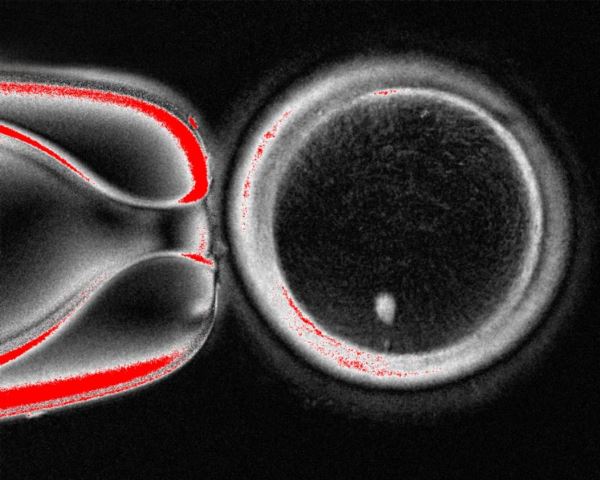

Прорыв в рождаемости: клетки кожи превратили в яйцеклеткиЧеловеческая яйцеклетка, созданная с помощью переноса ядра соматической клетки, процесса, впервые применённого при клонировании овечки Долли в 1990-х годах

Эта работа основана на клонировании, впервые осуществлённом в 1990-х годах в Институте Рослина в Шотландии. Команда под руководством Иэна Уилмута использовала перенос ядра соматической клетки для создания овечки Долли. Процесс включал извлечение ядра из клетки взрослой овцы и помещение его в яйцеклетку овцы, из которой было удалено собственное ядро. Полученная яйцеклетка была выношена суррогатной матерью Долли.

Команда из Орегона использовала аналогичный подход, собрав кожные клетки у женщин и удалив из каждой ядро. Ядро содержит 46 хромосом, которые несут около 20 000 генов, составляющих генетический код человека. Каждое ядро кожной клетки было помещено в здоровую донорскую яйцеклетку, из которой было удалено собственное ядро.